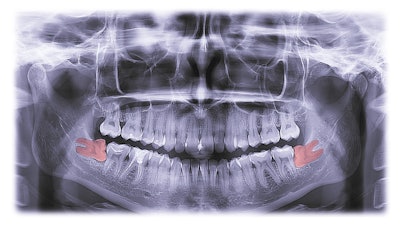

Orthodontists may be more likely to support early extraction of third molars to prevent crowding and cavities, while oral surgeons focus on avoiding pericoronitis and infections. This study was recently published in BMC Oral Health.

Orthodontists and oral surgeons differed in their reasons for extracting partially impacted molars. Orthodontists focused on preventing late dental crowding, while oral surgeons prioritized risks like pregnancy symptoms and infection (p < 0.05). Both groups agreed on extracting fully impacted molars for certain risks, except for focal infection, where oral surgeons were more concerned (p < 0.05), according to the results.